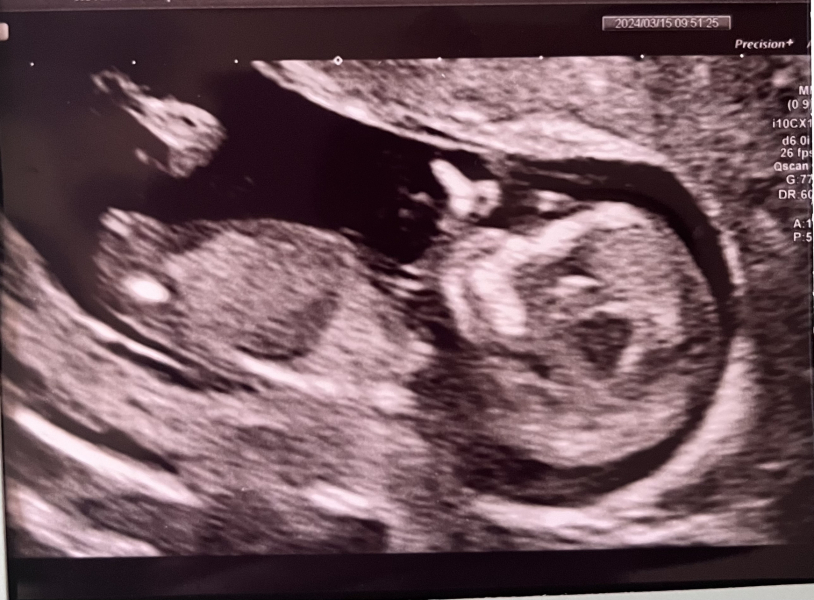

BeautyAndTheBump1 · 15/03/2024 15:44

Congratulations everyone on your scans! 🥰

I had mine and everything went well, the sonographer said the baby was laid in a great position so was snapping away to get some nice pics for us! They managed to get my bloods first attempt too and going by my last scan baby should've been measuring 12+2 or 12+3 but was measuring 12+6 today (some measurements were 13 and 13+1 but the sonographer used the lowest one) so very happy all around! Puts my due date at 21st September